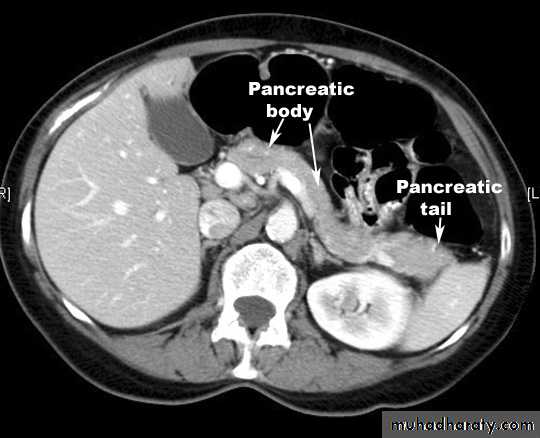

Made up of head, neck body and tail

Retroperitoneal

Head lies in the ‘C’ of the duodenum

also overlies IVC, L2 vertebra, medial aorta and superior mesenteric vessels

Behind the neck splenic veins joins superior mesenteric vein to form portal vein

Pancreatic duct closely related to common bile duct